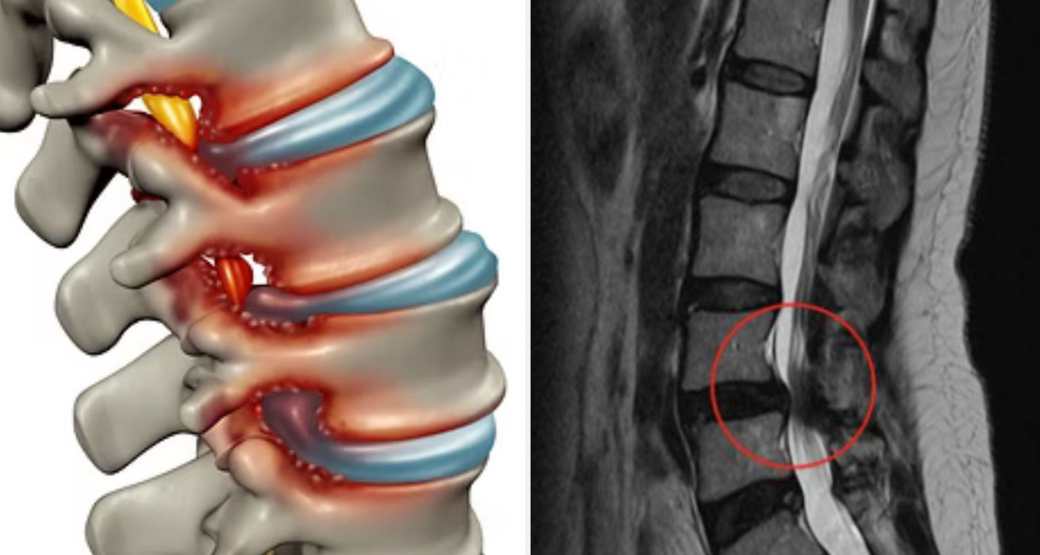

Caso clínico: Compressão radicular em L4-L5, à direita

Paciente idosa, 78, ao ser medicada, apresentava sintomatologia na região posterior do membro inferior direito e na face lateral da coxa direita.

Segundo o doutor Bastos, esses sinais direcionaram a equipe médica, para o envolvimento de duas raízes nervosas principais: a L4 e a L5.

Na Ressonância Magnética e na Tomografia, observaram uma artrose bastante avançada no canal lateral direito, especialmente entre as vértebras L4 e L5.

“Essa artrose, compromete os processos articulares superiores e inferiores, conhecidos como SAP e AP e, justamente, à frente dessas estruturas está localizada a raiz descendente de L5, explicando toda a sintomatologia da paciente”, descreve Bastos.